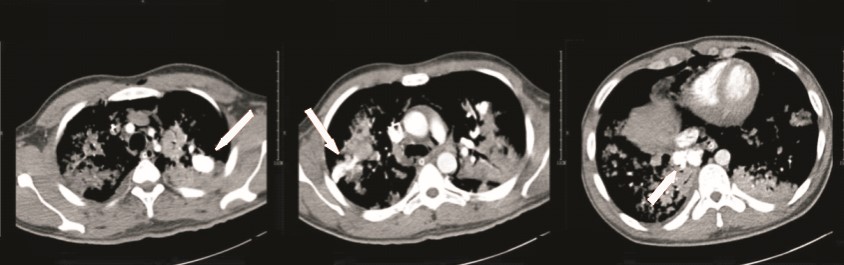

患者男性,25岁,因“突发抽搐后摔倒3 h余”于2014年2月23日诊断“外伤性硬膜下血肿”入我院神经外科,否认既往重大疾病史。急诊头颅计算机断层扫描(computed tomography,CT)及核磁共振成像(magnetic resonance imaging,MRI)均提示“左侧额颞部少量硬膜下血肿”。入院时患者浅昏迷,躁动不安,格拉斯哥昏迷评分(glasgow coma scale,GCS)11分,双侧瞳孔等大,光反射灵敏,两肺听诊未闻及明显干湿啰音,心律齐,无明显杂音,四肢均有活动,杵状指。入院后患者氧饱和度偏低,不吸氧时指脉氧饱和度波动在85%~90%之间,血常规:白细胞计数 10.4×109 L-1、中性粒比例 76.4%、血红蛋白 153 g/L,肝肾功能均正常范围,考虑患者有杵状指,予预约心脏彩超。入院第二日(2月24日),患者神志转清,有指令动作,对答切题,已可下床活动。2月27日患者在家属搀扶下上厕所时,突发心搏骤停,当时立即予以气管插管以及持续胸外心脏按压等心肺复苏抢救,约110 min左右,患者恢复自主心律并转入ICU进一步抢救及治疗。入ICU时患者双侧瞳孔等大,光反射存在,并随即出现四肢躁动,遂予持续镇痛镇静治疗,并予亚低温脑保护(头部冰帽及盐酸氯丙嗪+异丙嗪静脉维持,维持体温在34 ℃左右),小剂量去甲肾上腺素 维持MAP在90 mmHg(1 mmHg=0.133 kPa)左右,机械通气支持等治疗,患者氧合、循环基本稳定,亚低温治疗48 h左右(3月1日)予复温,患者有自主睁眼,四肢均有活动,期间予床边心脏超声检查(采用右侧锁骨下静脉注射5%碳酸氢钠溶液+维生素C微泡造影)发现左室微泡显影,考虑肺动静脉瘘可能(图 1),予预约胸部增强CT检查,3月3日中午,患者突发大咯血,咯血量达近800 mL,予提高呼吸机支持条件等抢救处理后患者咯血停止,氧饱和度维持在90%以上,予急诊肺动脉增强CT扫描发现患者多发肺动静脉瘘,分别位于左上肺、右上肺及右下肺(图 2),随即组织本院胸外科、介入治疗科以及心内科等相关科室讨论后考虑患者肺动静脉多发,手术治疗需切除肺叶面积极大,故首选介入栓塞治疗,经家属签字同意后,当天即予急诊数字减影血管造影(digital subtraction angiography,DSA),术中见患者左上、右下肺动静脉瘘均为双支动静脉瘘畸形,右上造影未见畸形血管,考虑血栓形成可能;尝试左上及右下肺动静脉瘘弹簧圈栓塞治疗,最终左上肺动静脉瘘栓塞成功(图 3),右下肺动静脉瘘管径过大,血流速极快,弹簧圈(本院最大直径)无法固定(图 4),漂移至右髂外动脉,予床边动脉切开取出后结束治疗返回病房。再次告知家属拟行开胸肺动静脉瘘切除手术治疗(右下肺),家属因费用问题拒绝手术治疗,至3月5日,患者再次出现大咯血,抢救无效死亡。

箭头示弹簧圈栓塞失败漂移至右侧髂外动脉 图 4 患者右下肺DSA及尝试栓塞治疗